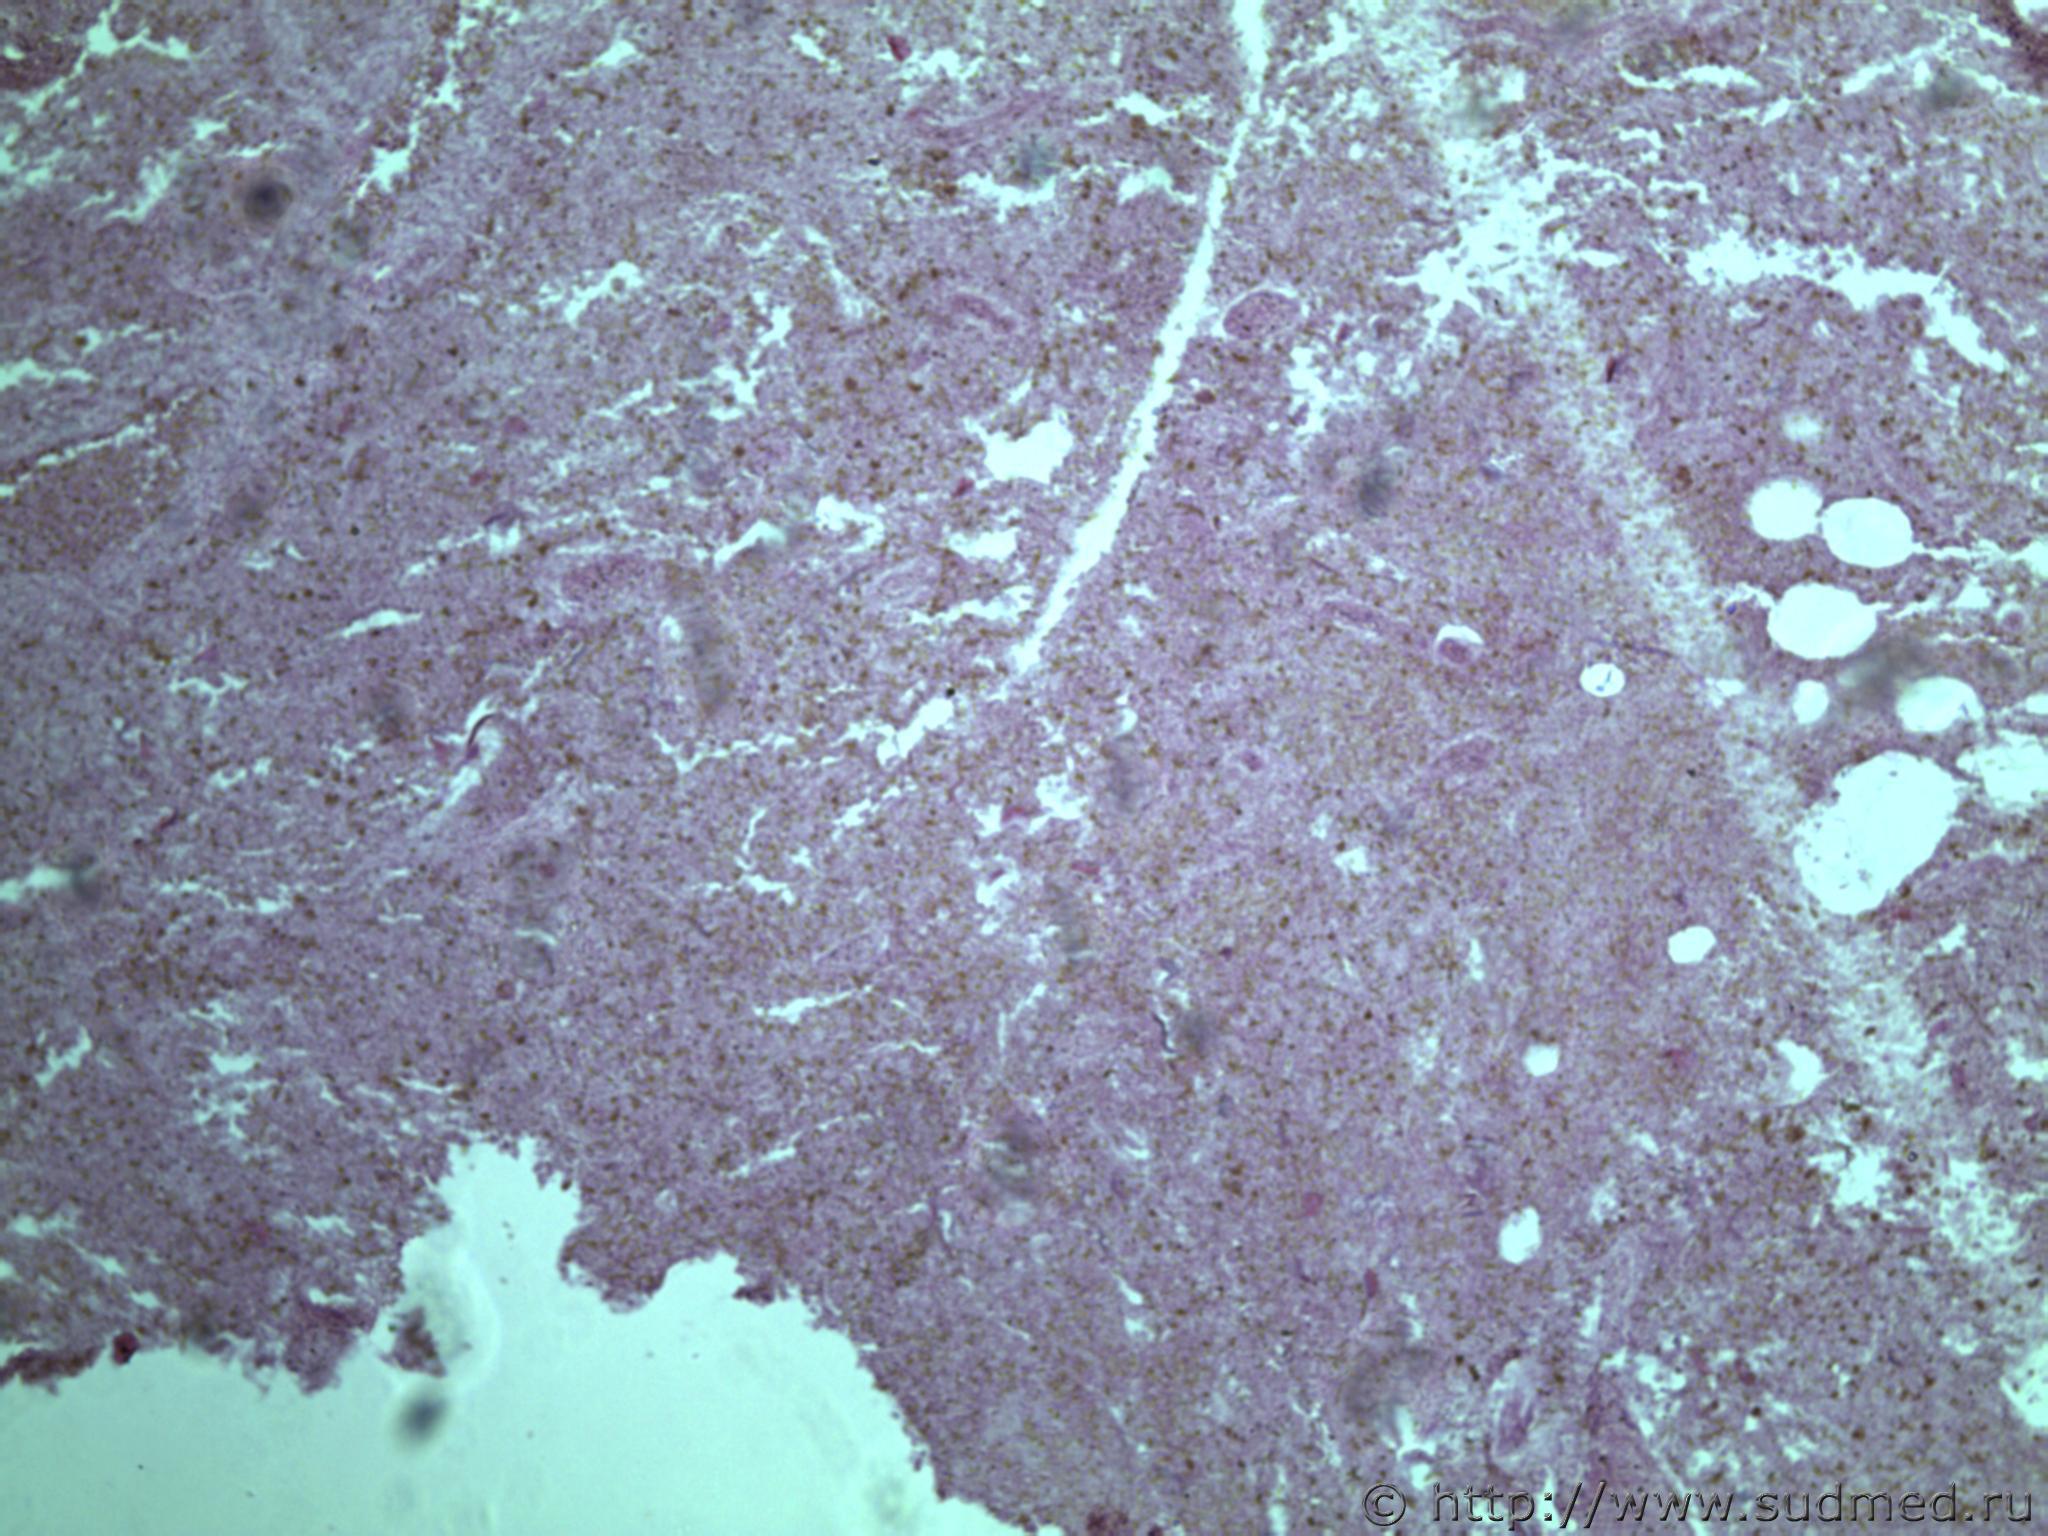

всем здравствуйте. хотела бы знать ваши мнения. провожу экспертизу. препараты как и труп новорожденного гнилые либо в аутолизе страшном. в легком картина такова, что ткань "плотная". просвет различимых альвеол в виде щелей и по всем полям зрения элементы околоплодных вод. одна артерия пуповины спазмирована. остальные сосуды непонятно : просвет их спавшийся но без признаков спазма. они как будто сплющены. да и сама пуповина в виде тонкого тяжа, видно из-за гнилостных изменений. под тмо спинного мозга признаки кровоизлияния, как и в коже с шеи. в коже головы с полнокровием отдельных сосудов. мать утверждает что ребенок после родов не сразу но все же шевелился и кричал. хотя перед этим он выпал у нее из матки на пол, ударившись головой. и со слов матери у него была пена изо рта и он хрипел.

Судебная медицина - Прикрепленное изображение Судебная медицина - Прикрепленное изображениеСудебная медицина - Прикрепленное изображениеСудебная медицина - Прикрепленное изображениеСудебная медицина - Прикрепленное изображение

Плохо,материал гнилой.

Остановился бы на дышавшем лёгком.

5 фото в сообщении №4 и 8 фото в сообщении №5 не наводит ли на мысль о дышавшем лёгком ?

Про остальные фото молчу,там или ничего не видно или же есть оптически пустые пузыри,что вероятнее всего,проявления гниения.